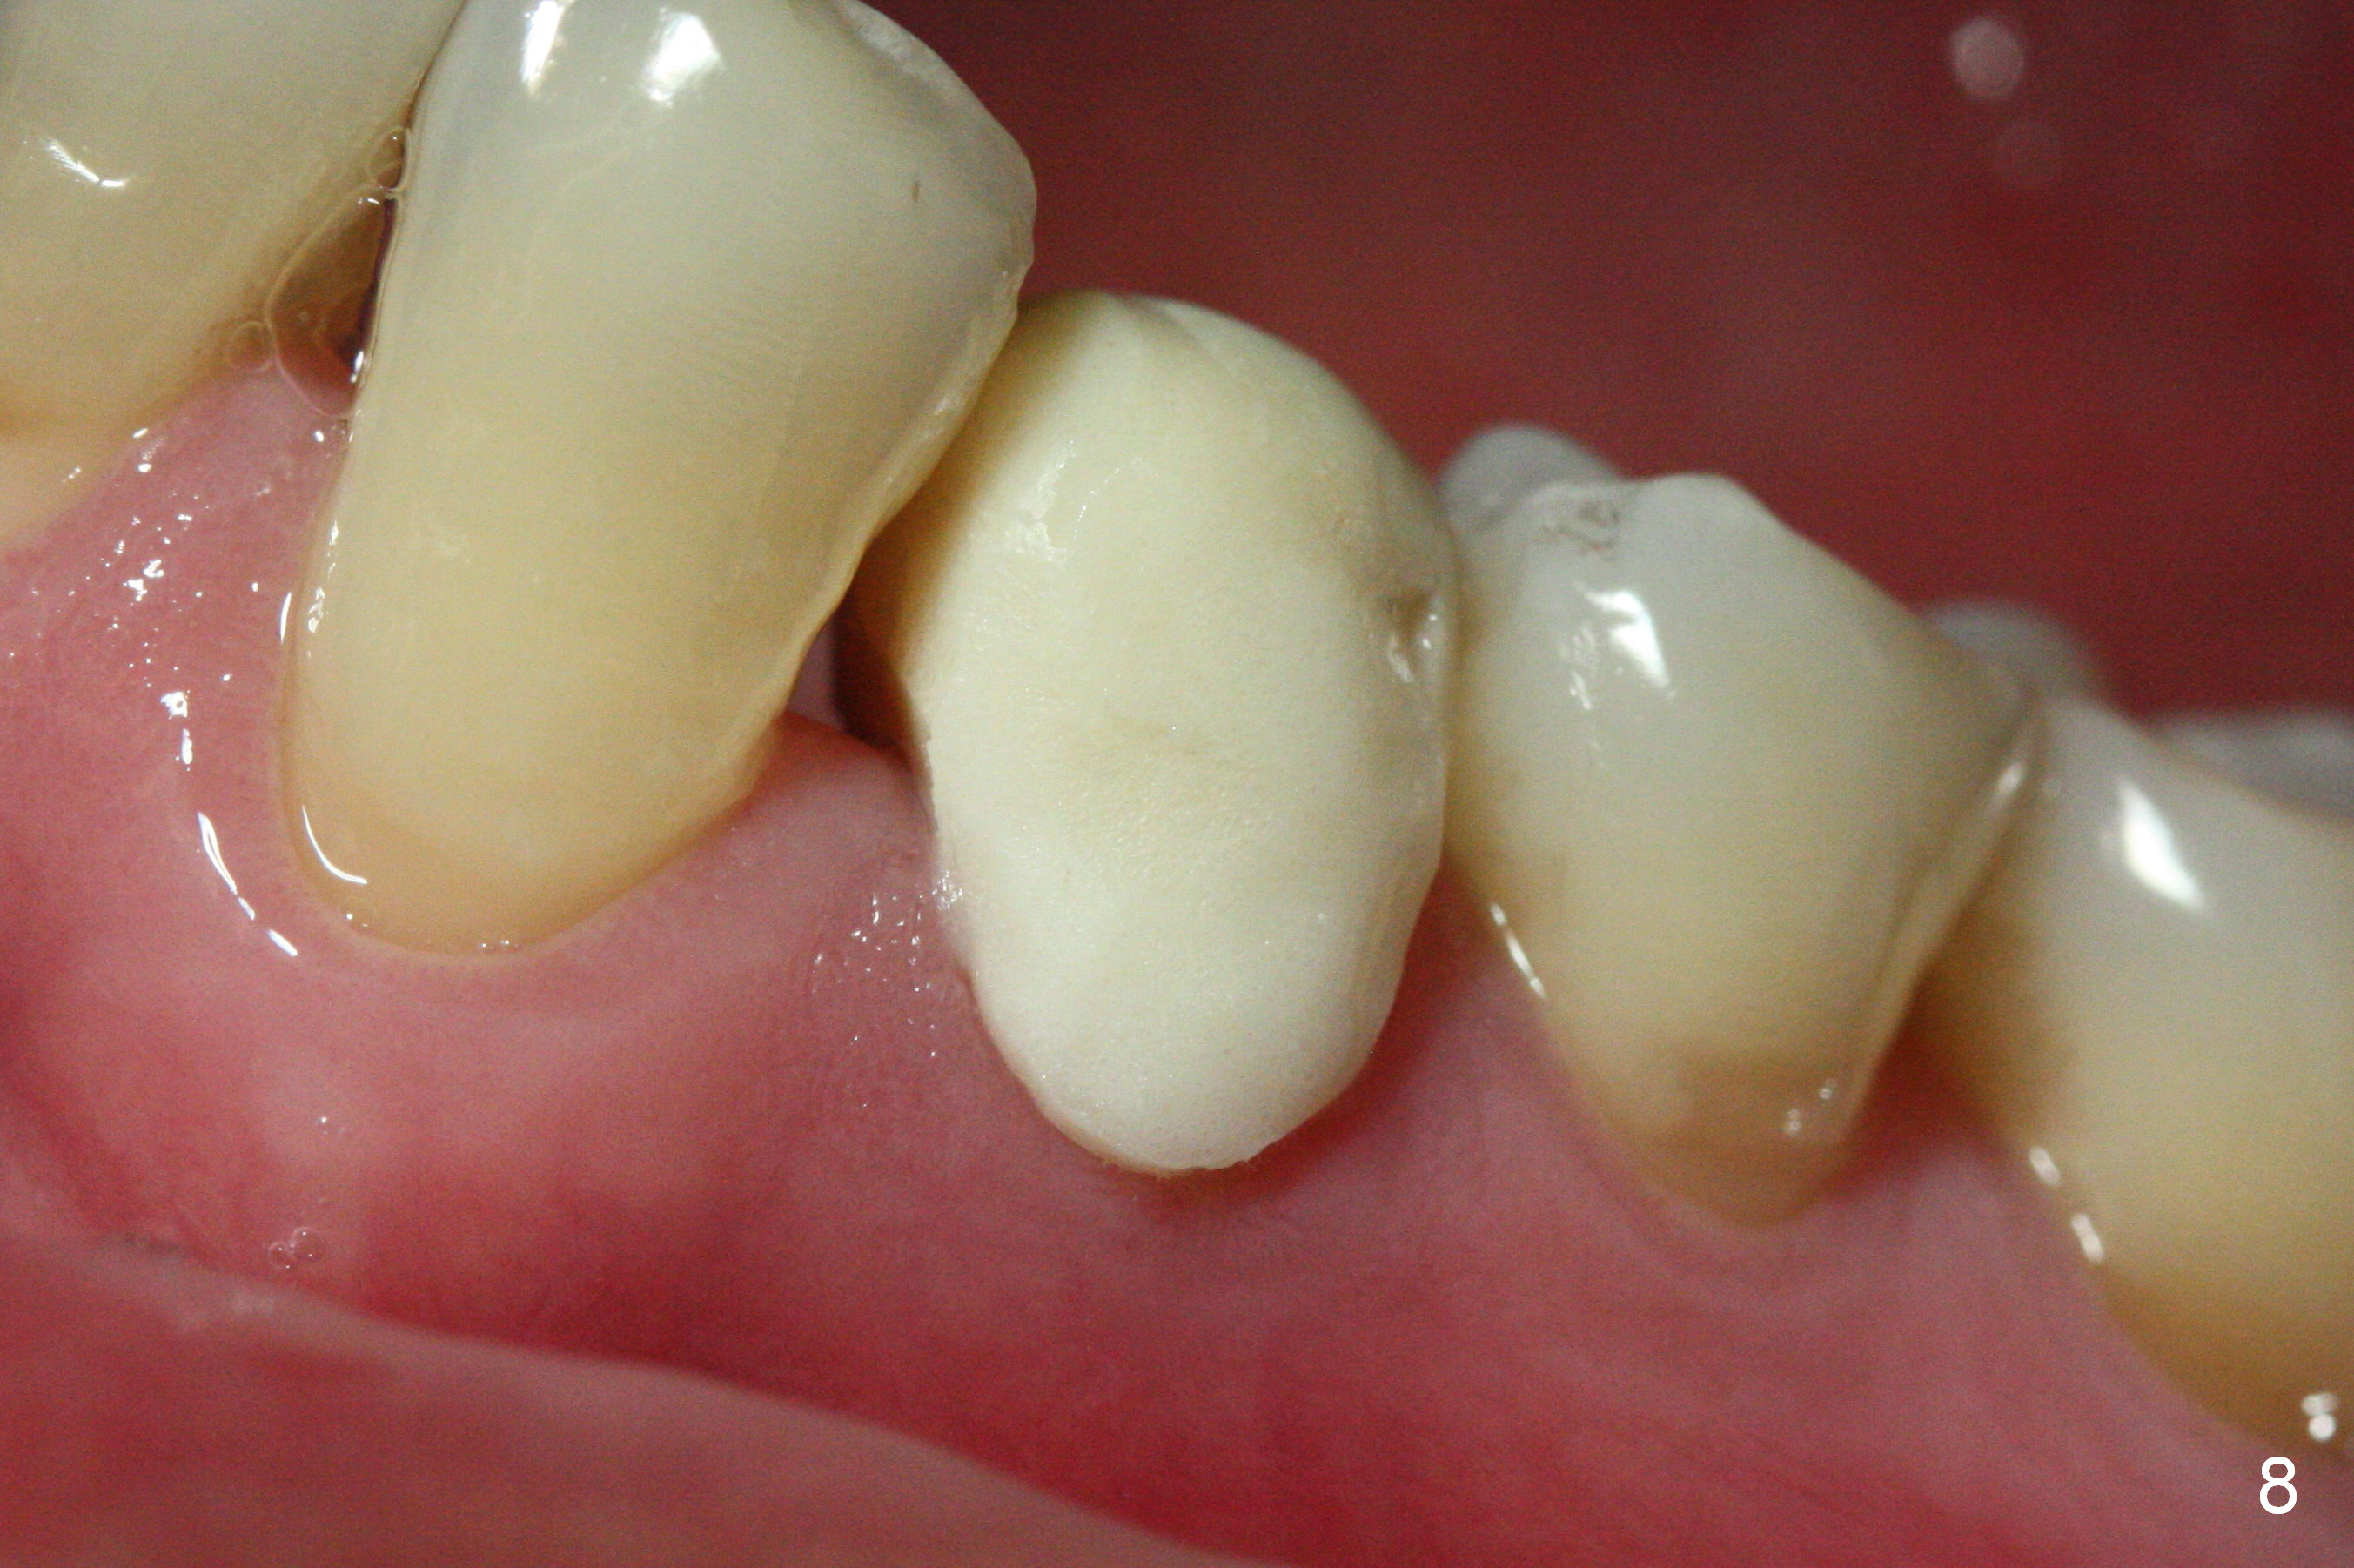

The patient returns for provisional revision 2 weeks postop (Fig.6).  The bone graft remains in place (Fig.7).  The buccal margin of the provisional is reduced (Fig.8).